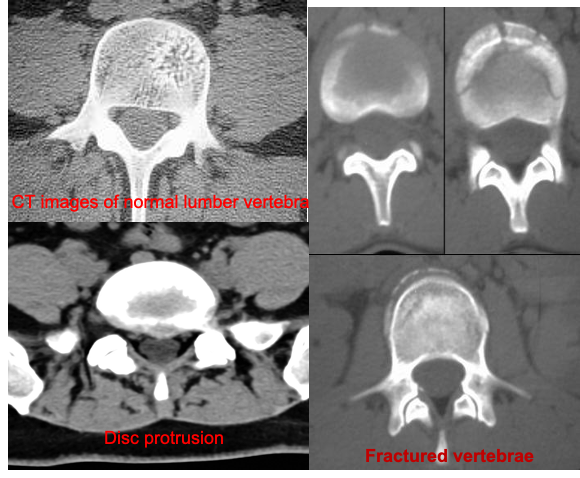

- Cross-sectional images are obtained of the target areas.

- Much detailed information regarding bony and soft tissues

Better in visualizing (Compared to Plain radiograph)

- Degenerative or aging changes

- Herniated discs

- Fractures